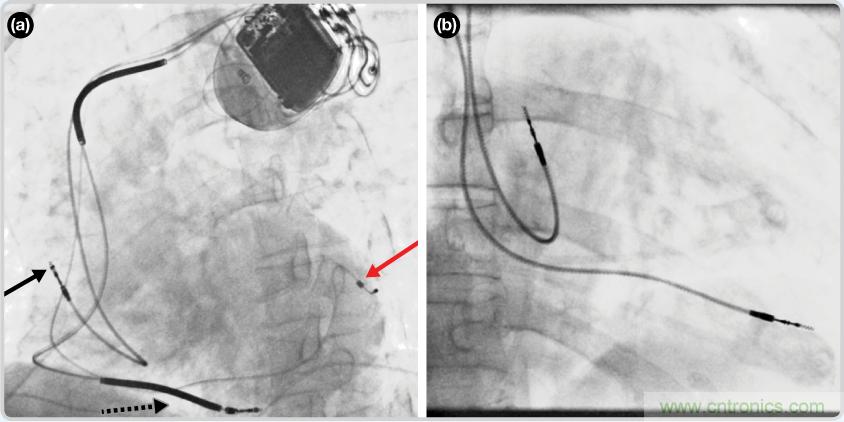

如果心臟這種機(jī)電系統(tǒng)存在缺陷,則可能導(dǎo)致諸多心臟問題。例如,當(dāng)心臟搏動(dòng)過慢或者不搏動(dòng)時(shí),就是心動(dòng)過緩。對于這種狀況,典型的手術(shù)治療方法是在患者胸部皮下植入一個(gè)起搏器(脈沖發(fā)生器),并將心內(nèi)膜導(dǎo)聯(lián)線通過靜脈直接引導(dǎo)至心臟,如圖3所示。

圖3. 植入式起搏器的位置以及不同種類起搏器的導(dǎo)聯(lián)線 (RA—right atrium, RV—right ventricle, LV—left ventricle)

CRT器件在圖4(a)中的透視圖像中可以看見。醫(yī)師就是利用這種影像來放置導(dǎo)聯(lián)線的。對于非專業(yè)人士來說,這種影像是很難解讀的。可以看到心臟淡淡的輪廓——這是搏動(dòng)中的心臟的靜態(tài)視圖。起搏器位于右心房上,心臟頂點(diǎn)指向右下方。在這個(gè)典型的導(dǎo)聯(lián)線放置實(shí)例中,黑色箭頭指向右心房導(dǎo)聯(lián)線。虛線黑色箭頭指向右心室導(dǎo)聯(lián)線。紅色箭頭標(biāo)示的導(dǎo)聯(lián)線只能看到一部分,這是左心室導(dǎo)聯(lián)線(紅箭頭指向電極尖端)。圖4(b)展示的是雙腔起搏器的典型導(dǎo)聯(lián)線放置透視圖像。右心房導(dǎo)聯(lián)線指向上方,置于右心房中。右心室導(dǎo)聯(lián)線則位于右心室頂部。

圖4. 起搏器導(dǎo)聯(lián)線放置的透視圖像3 (a). 單腔起搏器;(b).雙腔起搏器